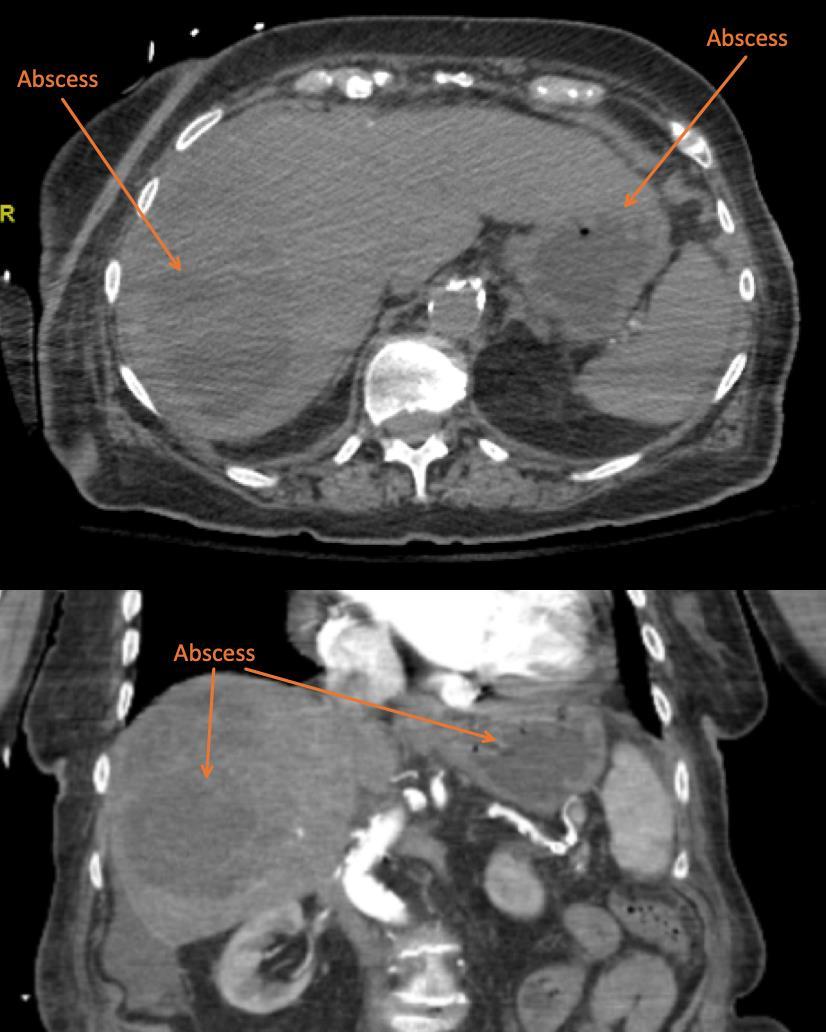

115 Point-of-care Ultrasound Identification of Hepatic Abscess in the Emergency Department

M Blomquist, T Brinkerhoff, D Weech, H Choi